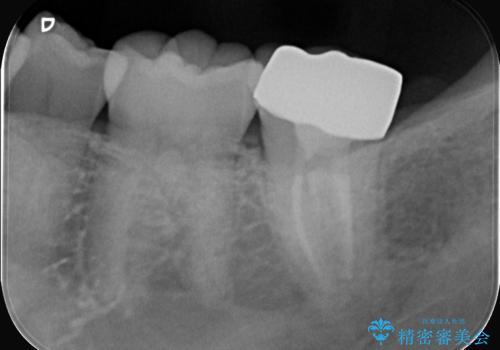

- 昨日からのズキズキとした激しい痛みを主訴にご来院されました。レントゲンおよび歯髄診察の結果、不可逆性の歯髄炎(歯の神経の重度の炎症)と診断。歯を残すことを第一に、まず痛みの原因である神経を取り除く根管治療を提案しました。また、虫歯が歯肉の下まで深く進行していたため、根管治療後に歯周外科処置を行い、最終的に精密なセラミッククラウンで修復する、総合的な治療計画を立案しました。

治療はまず、根管治療から始め、感染した神経を徹底的に除去することで、痛みをすぐに解消しました。再発を防ぐため、ラバーダムや顕微鏡を使って、根管内を丁寧に、そして精密に処置しました。次に、深い部分の虫歯を確実に治療するため、歯周外科処置を行い、治療しやすい環境を整えました。最後に、機能と見た目に優れたセラミッククラウンを作製・装着。根管治療から外科処置、審美修復までを一貫して行うことで、再発リスクの低い、長期的に安定して使える奥歯を取り戻していただけました。